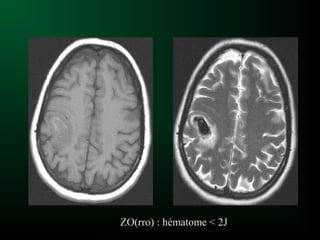

Z O R R O

Hématome au stade Hyperaigu :J0

Hématome à 1ZO(rro) : hématome < 2J

(zo)RR(o) :

Hématome subaigu = 2 sem.

T1

T2 Flair T2*